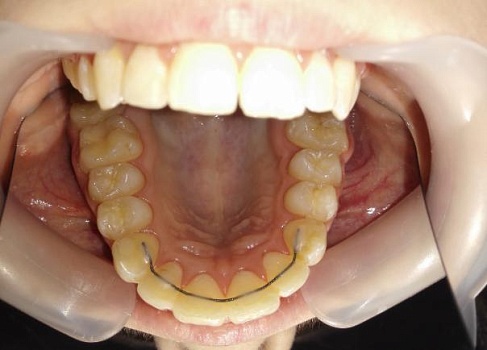

Сохранить зубы и пародонт помогает правильная гигиена полости рта дома и в кресле стоматолога, а также своевременное протезирование и имплантация, которые замещают удаленные зубы и равномерно распределяют жевательную нагрузку, не позволяя костной ткани атрофироваться.

Таким образом, по мнению стоматологов, риск возникновения болезней десен на 80% зависит от сознательности самого пациента.